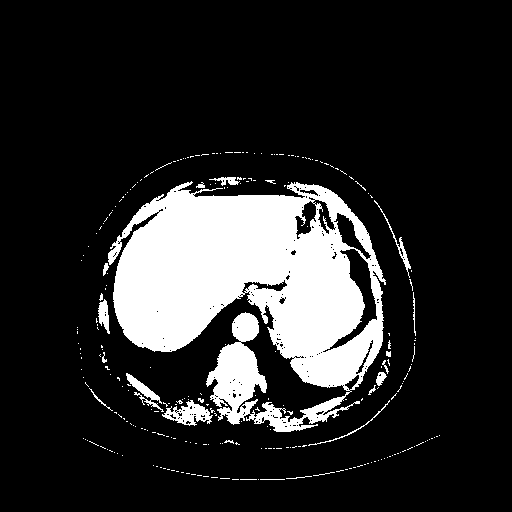

Reconstructed NATIVE CT scan (cycle consistency)

Full window (WL 1023.5, WW 4095 β†’ Low βˆ’1024, High +3071)

Actual HU range: [-1024.0, 3071.0]